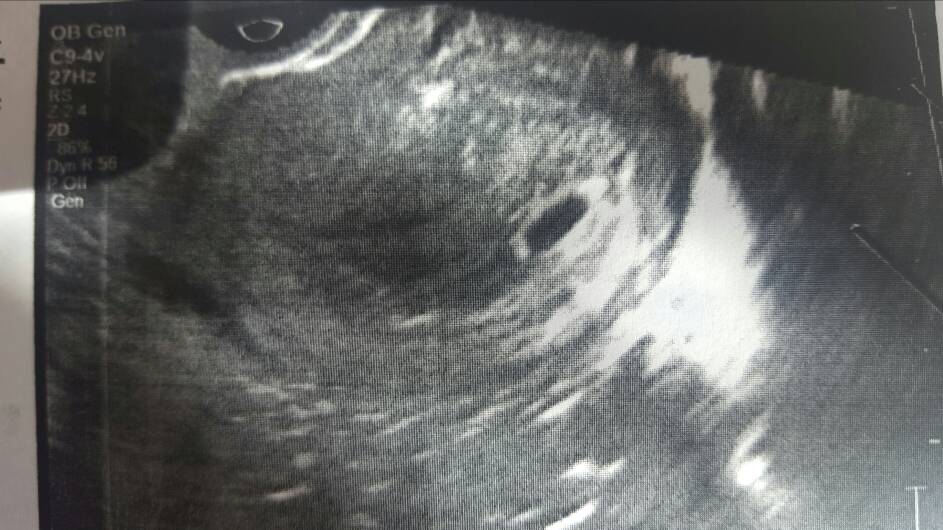

Kurcze u mnie nie ma widać zarodka [emoji22] jest pecherzyk, ładny ale pusty... mam czekać na kolejną wizytę...

@iwilleatyou a jaki Ty masz dokładnie dzień ciąży? Bo mój pecherzyk wygląda identycznie jak Twój.

img]

Może chodziło mu o to, że jest puste w tym momencie, ale żeby poczekać bo jest jeszcze czas??? Tzn, nie widać dzidzi, nie że puste... zakręciłam, przepraszam.